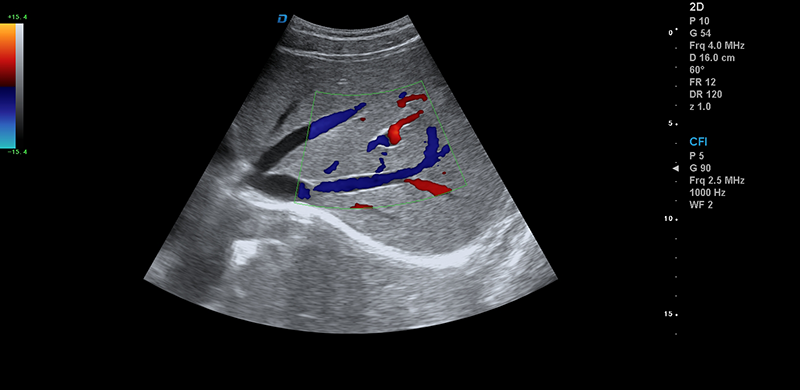

彩超機腎臟血流檢測圖

腎臟血流